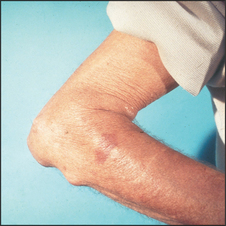

Examination of the hands is not complete without feeling for the subcutaneous nodules of rheumatoid arthritis near the elbows (see Figure 24.17). These are 0.5–3 centimetre firm, shotty,h non-tender lumps that occur typically over the olecranon. They may be attached to bone. They are found in rheumatoid factor-positive rheumatoid arthritis. Rheumatoid nodules are areas of fibrinoid necrosis with a characteristic histological appearance and are probably initiated by a small vessel vasculitis. They are localised by trauma but can occur elsewhere, especially attached to tendons, over pressure areas in the hands or feet, in the lung, pleura, myocardium or vocal cords. They are most commonly found firmly attached over the proximal ulna, just distal to the elbow. Occasionally they are within the olecranon bursa and can be moved freely within it. The combination of arthritis and nodules suggests the diagnostic possibilities outlined in List 24.5.